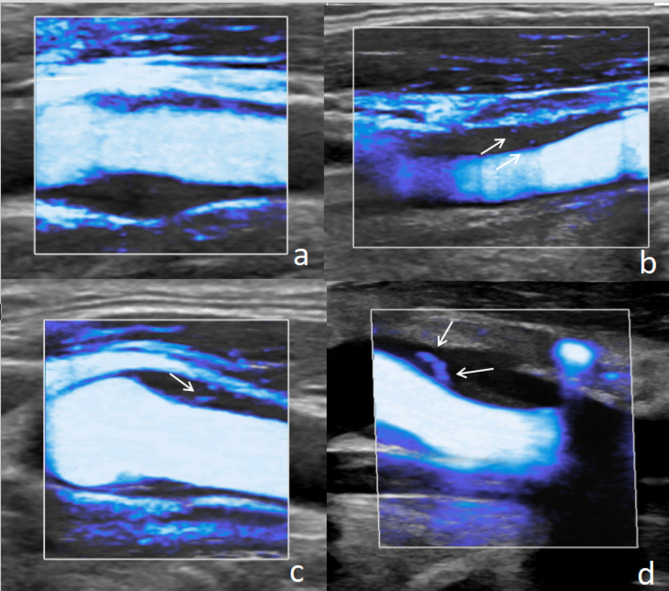

易损斑块是急性缺血性事件的重要危险因素,斑块内新生血管(IPN)是评价斑块易损的重要指标。本文综述了IPN在评估颈动脉斑块易损性中的重要性、IPN超声检查的现状以及IPN超声成像技术的进展,包括:高超的微血管成像技术;对比度增强超声;平面波超灵敏血流成像;超声靶向微泡破坏;超声超分辨率成像。旨在为缺血性心脑血管事件的预防和治疗提供参考。

Vulnerable plaques are significant risk factors for acute ischemic events, and intraplaque neovascularization (IPN) is an important indicator for evaluating plaque vulnerability. This review summarizes the importance of IPN in the assessment of carotid plaque vulnerability, the current status of ultrasound examination of IPN, and the technical advancements in ultrasound imaging of IPN, These techniques include: Superb micro-vascular imaging; Contrast-enhanced ultrasound; Plane wave ultra-sensitive blood flow imaging; Ultrasound-targeted microbubble destruction; Ultrasound Super-Resolution Imaging. Aiming to provide a reference for the prevention and treatment of ischemic cardiovascular and cerebrovascular events.